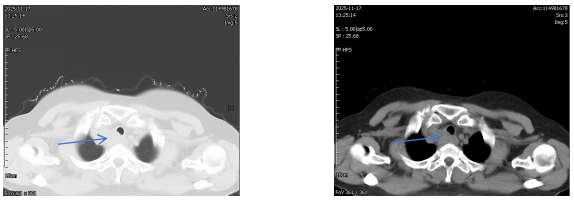

治疗前胸部CT

62岁的郑女士近一月来进食时总有食物下咽不畅感,伴有明显哽咽。当地医院胸部增强CT提示食管上段有一约3.7×2.6CM占位性病变,影像报告“不除外食管癌,且可能累及气管后壁”。随后的PET-CT更显示该病灶糖代谢异常增高,代谢活性值高达14.4,强烈指向恶性肿瘤可能。这一系列检查结果让患者及家人陷入焦虑与恐惧。

然而,当通过胃镜直视食管内部时,发现占位隆起更像来自外部压迫,表面光滑。超声胃镜进一步揭示病灶位于食管外,是与食管、气管紧密相邻的不规则低回声区。虽然仍不能排除恶性肿瘤的可能,但病灶位置为诊断带来新的思考。